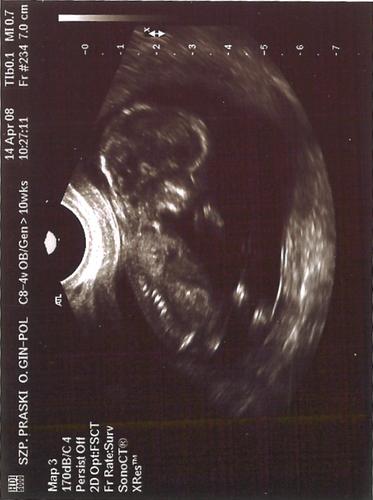

Ja też szykuję się na październik i to też 12 tydzień - własnie jestem po USG. Faktycznie przezycie niesamowite - gdy pani doktor pokazała dwie rączki i dwie nóżki mojego męża tak zatkało, że nie mógł sie odezwać - a ja w końcu uwierzyłam że zostanę mamą. Na razie diagnoza, że wszystko OK - prześwit karkowy malenki, nosek poteżny (chyba po tatusiu niestety...). Ale najwiekszy szok, że takie małe dzieciątko juz tak się rusza - fikało niesamowicie - pewnie adhd będzie....

). Pierwszy raz widzialam maleństwo w fazie płodowej. To było niesamowite. Widziałam jak przykładało rączkę do buzi (lekarz powiedział, że raczej jeszcze ssać kciuka nie mogło).Ależ to było urocze...